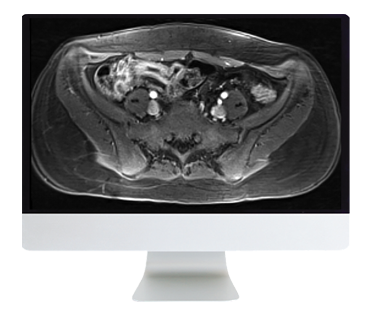

- ARRS A Guide to Bowel Imaging 2019 (CME VIDEOS) This course covers varied aspects of bowel imaging which will give the participant a comprehensive overview of different bowel pathologies. It covers imaging of the bowel in the emergency room, bowel ischemia, Crohn disease, bowel neoplasms, postoperative imaging, CT colonography, and role of molecular imaging in bowel pathologies. All modalities including fluoroscopy, CT, MR, and molecular imaging are discussed.

- After completing this course, the learner should be able to: Evaluate the role different modalities like fluoroscopy, CT, MR, and molecular imaging play in diagnosing bowel pathologies; Recognize imaging presentation of acute bowel conditions including bowel ischemia; Diagnose and characterize active and chronic Crohn disease on CT and MR enterography; Describe the imaging characteristics of various small bowel tumors; Optimize fluoroscopy techniques in diagnosing postoperative complications; Describe techniques to optimize CT colonography.

- Imaging of Crohn Disease—R. Sanyal